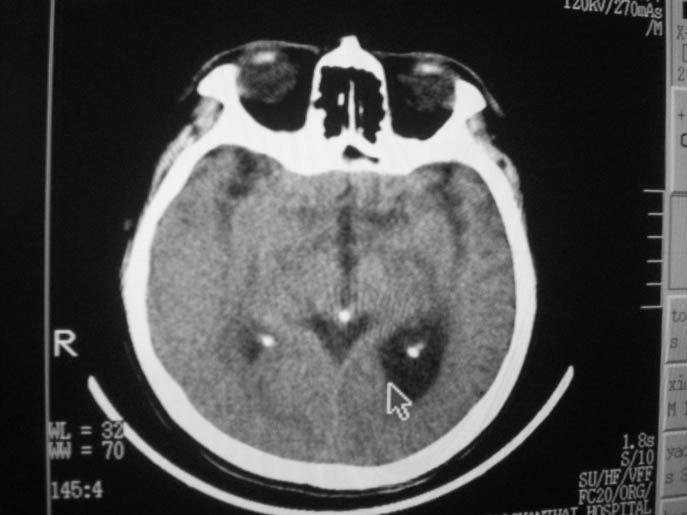

以下是引用卜一在2009-9-7 16:23:00的发言:[br]支持:胶质瘤伴出血!

以下是引用随光逐影在2009-9-8 7:40:00的发言:[br]考虑脑转移瘤或胶质瘤并肿瘤卒中;建议行ct增强扫描检查。

以下是引用熊熊在2009-9-7 18:31:00的发言:[br]胶质瘤伴出血[br]建议增强